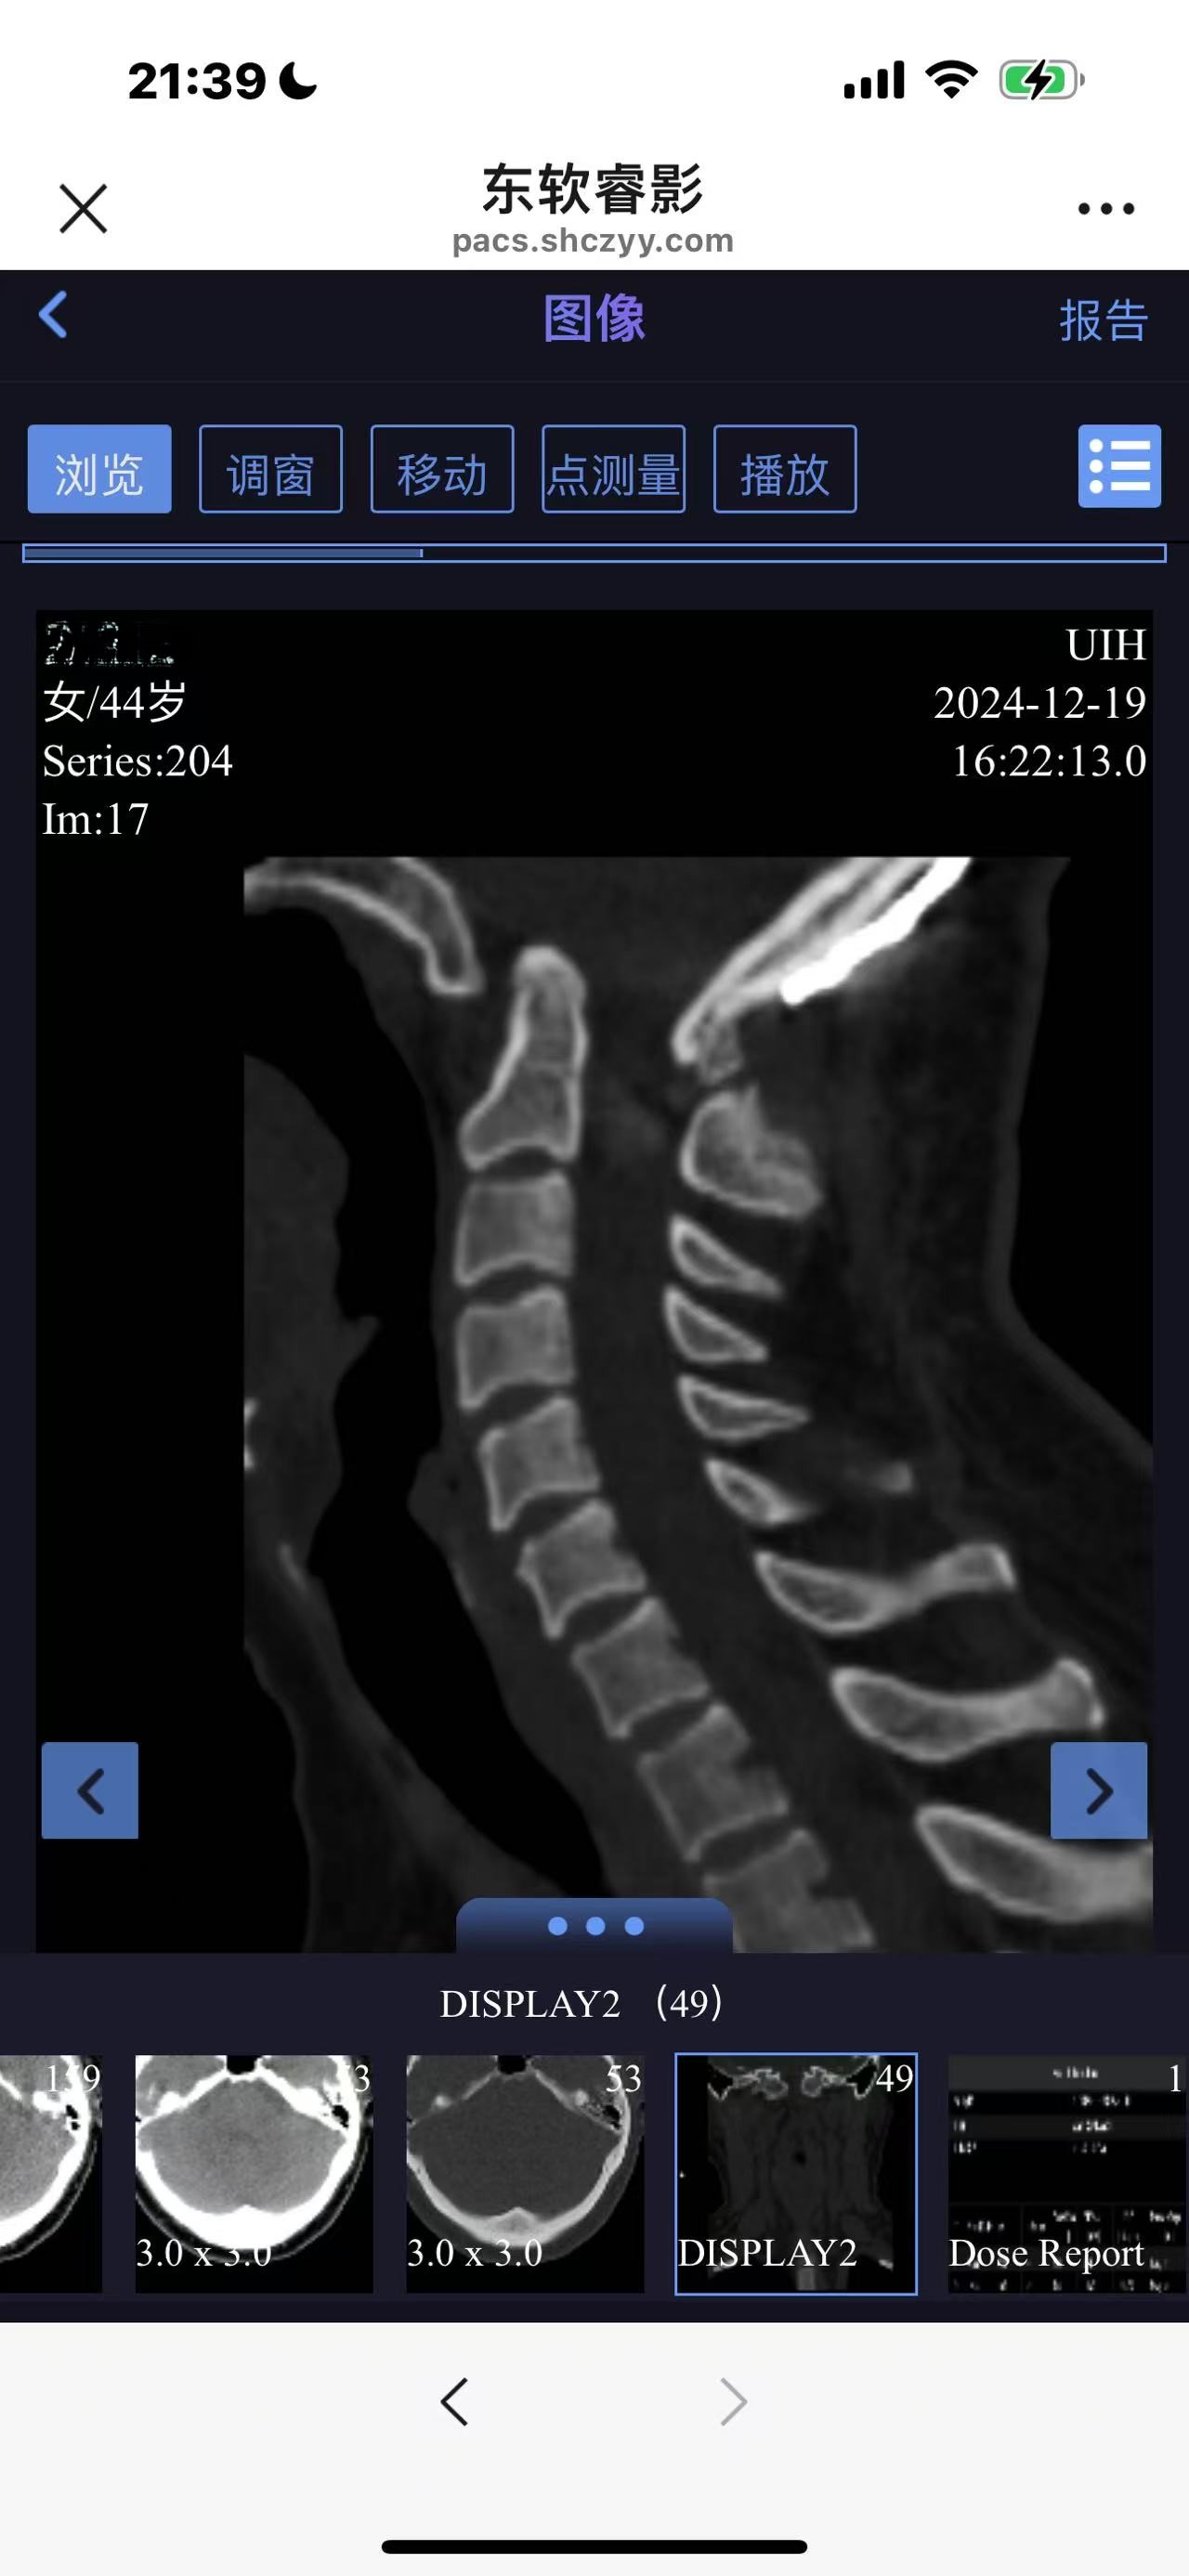

• 诊断:寰枢椎脱位

• 术后影像: